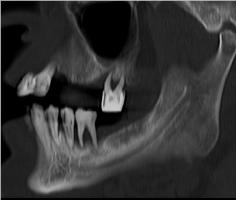

Патологія зубощелепної системи, планування імплантації зубів.

Дентальна КТ